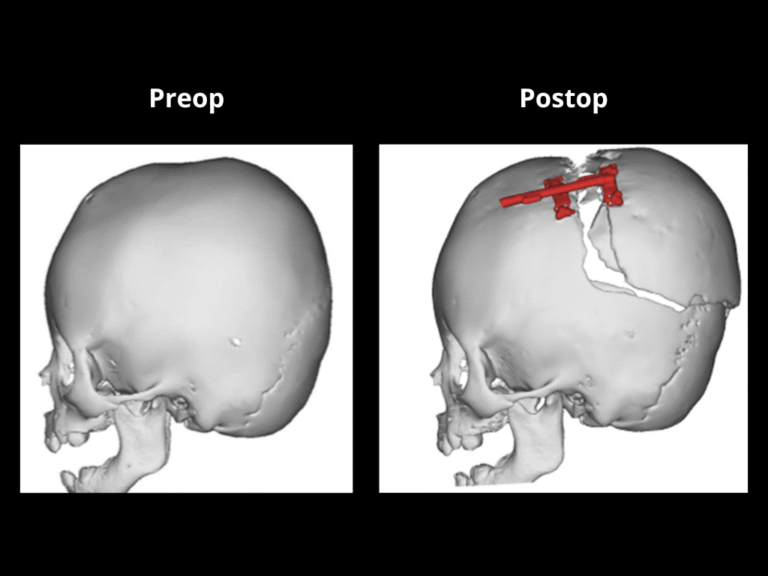

At El Paso Craniofacial Team, the primary treatment for craniosynostosis is surgery. First performed in the late 1800s, surgical approaches have continued to evolve and improve. The two main approaches are Calvarial Vault Remodel (CVR) and endoscopic-assisted surgery, with each tailored to the child’s age, the affected suture, and the severity of the condition.